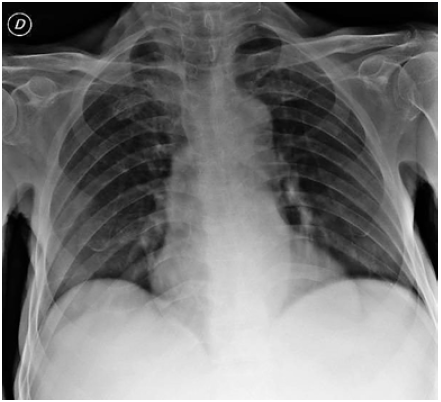

Al examen físico de ingreso se documentó ingurgitación yugular grado II y edema de miembros inferiores; no se encontraron marcadores de injuria miocárdica pero sí se evidenció hipotiroidismo primario de novo y enfermedad renal crónica categoría G3a (Tabla 1). Asimismo, se realizó un electrocardiograma que no mostró cambios sugestivos de evento coronario agudo, una radiografía de tórax que reveló ligera cardiomegalia sin consolidaciones ni masas (Figura 1) y un ecocardiograma transtorácico en el que se reportaron los siguientes hallazgos:

Radiografía de tórax que evidencia probables cambios espondiloartrósicos dorsales.

Figura 1: Radiografía de tórax que evidencia probables cambios espondiloartrósicos dorsales.

Fuente: Documento obtenido durante la realización del estudio.